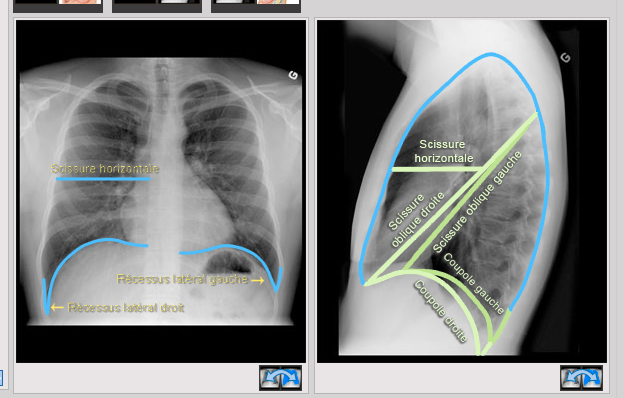

Où sont situées les coupoles diaphragmatiques ainsi que les scissures sur une radio?